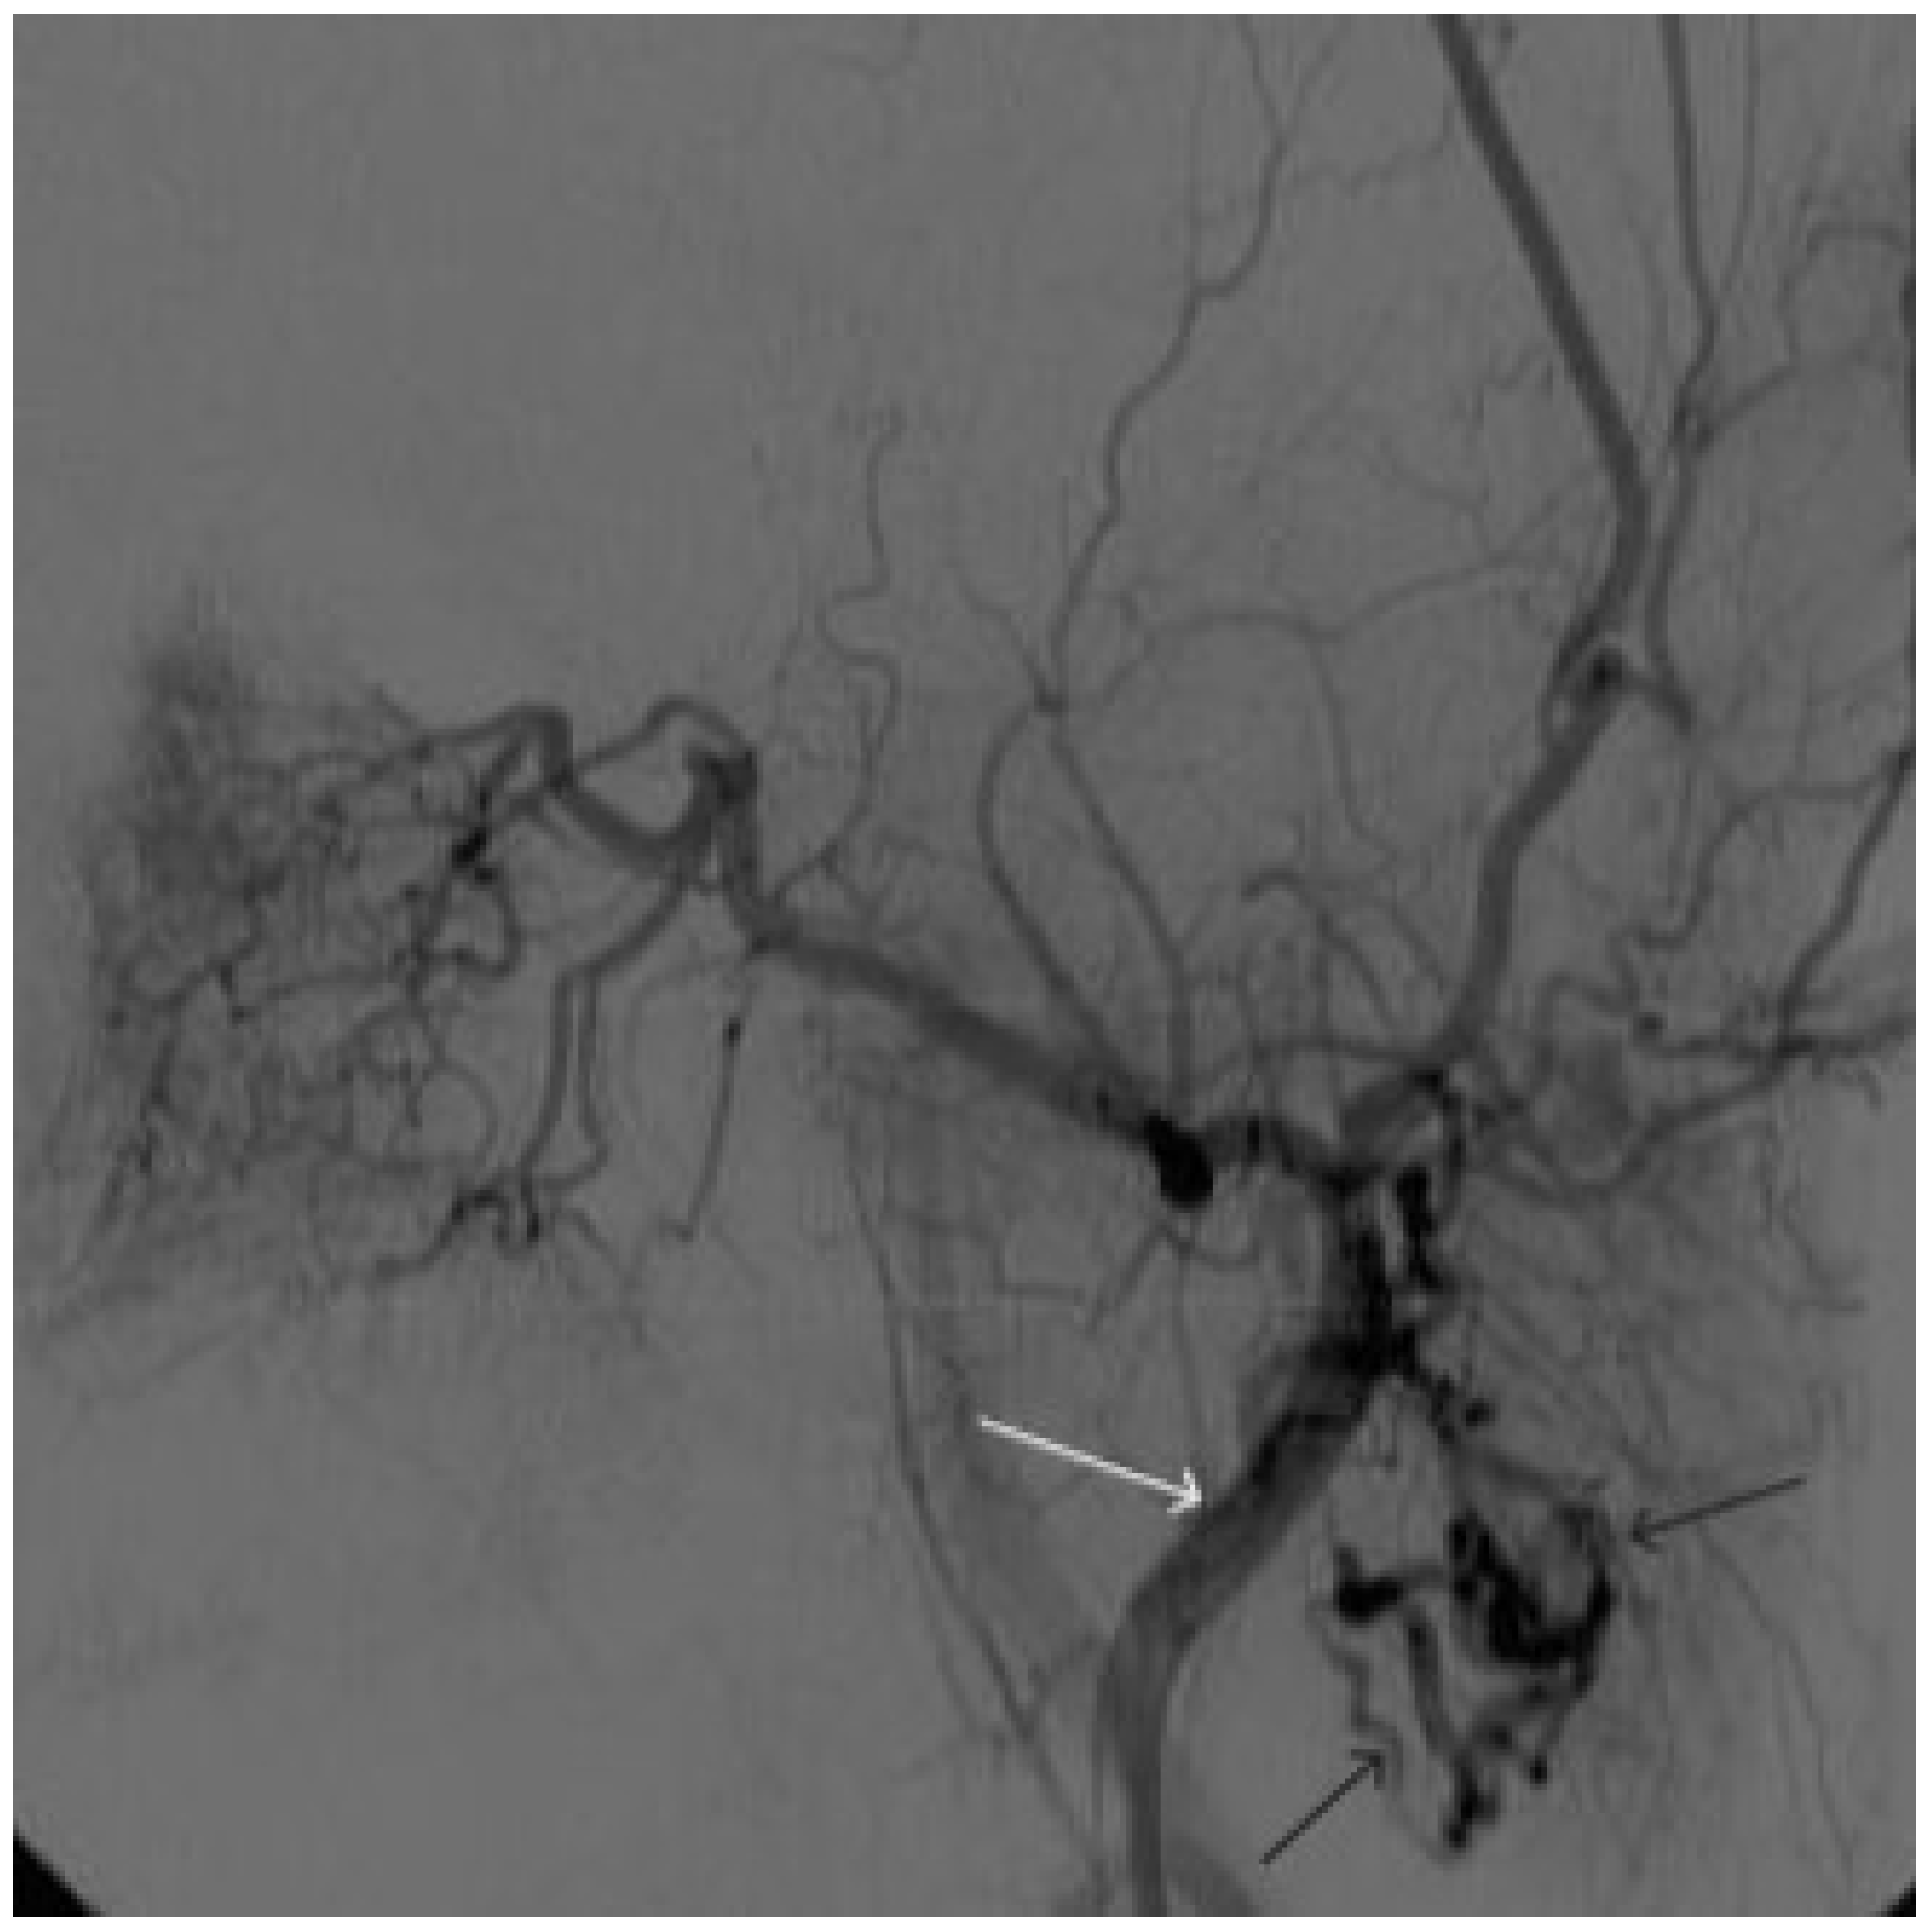

Figure 8. Digital subtraction angiography from the left external carotid artery, direct projection (white arrow indicates catheter in the left external carotid artery, black arrows indicate contrast AVM.

Figure 9. X-ray, direct projection (the white arrow indicates a microcatheter in the left external carotid artery, the black arrows indicate a complex of microcoils from the previous stage of embolization.

Figure 10. Digital subtraction angiography from the left external carotid artery, direct projection (white arrow indicates the left external carotid artery, black arrows indicate the boundaries of the filled AVM).